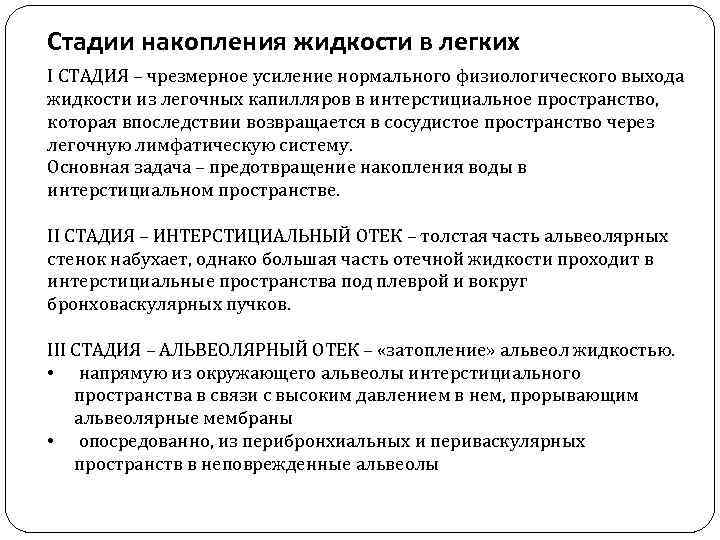

Стадии накопления жидкости в легких I СТАДИЯ – чрезмерное усиление нормального физиологического выхода жидкости из легочных капилляров в интерстициальное пространство, которая впоследствии возвращается в сосудистое пространство через легочную лимфатическую систему. Основная задача – предотвращение накопления воды в интерстициальном пространстве. II СТАДИЯ – ИНТЕРСТИЦИАЛЬНЫЙ ОТЕК – толстая часть альвеолярных стенок набухает, однако большая часть отечной жидкости проходит в интерстициальные пространства под плеврой и вокруг бронховаскулярных пучков. III СТАДИЯ – АЛЬВЕОЛЯРНЫЙ ОТЕК – «затопление» альвеол жидкостью. • напрямую из окружающего альвеолы интерстициального пространства в связи с высоким давлением в нем, прорывающим альвеолярные мембраны • опосредованно, из перибронхиальных и периваскулярных пространств в неповрежденные альвеолы

Стадии накопления жидкости в легких I СТАДИЯ – чрезмерное усиление нормального физиологического выхода жидкости из легочных капилляров в интерстициальное пространство, которая впоследствии возвращается в сосудистое пространство через легочную лимфатическую систему. Основная задача – предотвращение накопления воды в интерстициальном пространстве. II СТАДИЯ – ИНТЕРСТИЦИАЛЬНЫЙ ОТЕК – толстая часть альвеолярных стенок набухает, однако большая часть отечной жидкости проходит в интерстициальные пространства под плеврой и вокруг бронховаскулярных пучков. III СТАДИЯ – АЛЬВЕОЛЯРНЫЙ ОТЕК – «затопление» альвеол жидкостью. • напрямую из окружающего альвеолы интерстициального пространства в связи с высоким давлением в нем, прорывающим альвеолярные мембраны • опосредованно, из перибронхиальных и периваскулярных пространств в неповрежденные альвеолы